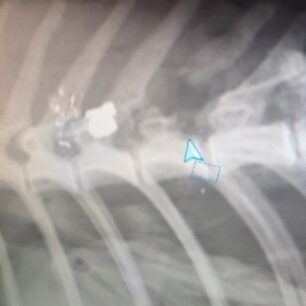

Το ζώο, όπως έδειξαν οι ακτινογραφίες, είχε πυροβοληθεί με αεροβόλο δύο φορές. Το ένα σφαιρίδιο είχε καρφωθεί στην σπονδυλική του στήλη και αν δεν είχε πάει επί τόπου ο εθελοντής διασώστης Κώστας Μαμασούλας, ώστε και να το πιάσει και να το μεταφέρει σε κτηνιατρική κλινική, η γάτα θα ήταν ήδη νεκρή και θα είχε μαρτυρικό θάνατο…

Οι πιθανότητες να περπατήσει είναι λιγες, ωστόσο αποφασίστηκε να κάνει το χειρουργείο και να του δώσουμε έστω αυτή την μικρή πιθανότητα ώστε να βγει η σφαίρα που είχε σφηνώσει στην σπονδυλική στήλη και να αποσυμπιεστεί. Τώρα το μόνο που μας μένει είναι να περιμένουμε, καθώς είναι πολύ δύσκολο ζώο και καθόλου συνεργάσιμο.».